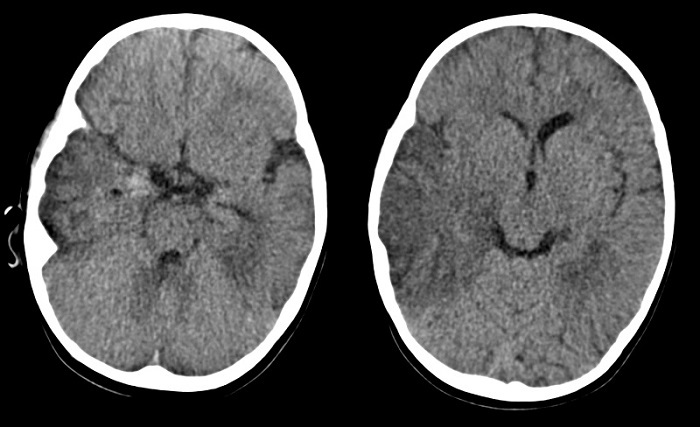

Inicialmente la paciente recibe tratamiento antibiótico intravenoso con cefuroxima ante la sospecha de discitis, que se descarta a las 48 horas del ingreso mediante gammagrafía ósea en la que no se objetivan alteraciones de significación patológica. Posteriormente ante la sospecha clínica de meningoencefalitis con persistencia de fiebre, somnolencia e irritabilidad, se inicia tratamiento antibiótico empírico con cefotaxima, vancomicina y aciclovir intravenosos. Se realiza tomografía computarizada (TC) craneal en el que se observan hipodensidades en las áreas parietotemporal derecha y temporal izquierda, con discreto efecto de masa, con pequeños focos hiperdensos sugestivos de hemorragia en punta del temporal derecho (Fig. 1). Dichos hallazgos sugieren una posible encefalitis herpética. Tras la TC craneal se decide realizar punción lumbar con los siguientes resultados en el líquido cefalorraquídeo (LCR): hematíes 3500/mm3, células nucleadas 150/mm3 (segmentados: 1%, linfocitos: 82%, células mononucleares: 17%), glucorraquia 0,40 g/l y proteinorraquia 1,01 g/l.

| Figura 1. Tomografía computarizada craneal sin contraste. Cortes axiales. Extensa hipodensidad temporoparietal derecha, con discreto efecto de masa sobre sistema ventricular derecho y leve desplazamiento de la línea media. Pequeños focos hiperdensos en la punta del temporal derechos, sugestivos de focos hemorrágicos. Hipodensidad temporobasal izquierda sin efecto de masa significativo |